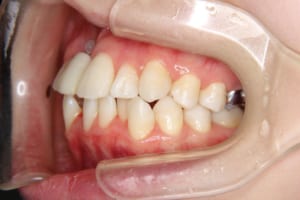

• Before

治療前